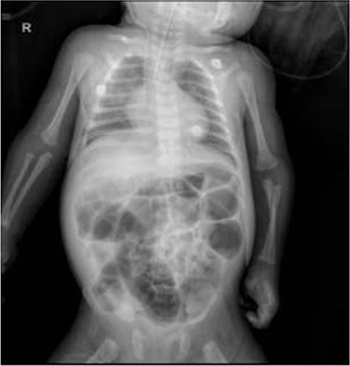

En el quinto día, se intentó la extubación, pero el paciente no toleró el procedimiento debido a la obstrucción del tubo orotraqueal con secreción sanguinolenta densa. Además, los episodios de tos quintosa se acentuaron. En el séptimo día, se agregó tratamiento antibiótico con Colistina debido a la identificación de una colonización/infección polimicrobiana por estudios de biología molecular mediante el uso de un panel filmarray que permitió la detección de Acinetobacter baumannii multirresistente Además, esta técnica molecular permitió la detección de S. marcescens y VSR. En el octavo día se obtuvo una radiografía de tórax de control donde se aprecian áreas con densidades anormales, que son heterogéneas y se encuentran principalmente en el campo pulmonar derecho, las cuales sugieren infección pulmonar (Figura 2). En el décimo día, se inició el tratamiento con morfina y clonazepam debido al síndrome de abstinencia. Después de una estancia prolongada en cuidados intensivos, en el día 14 se logró realizar la extubación de manera exitosa. Sin embargo, el paciente continuó recibiendo tratamiento y cuidados.